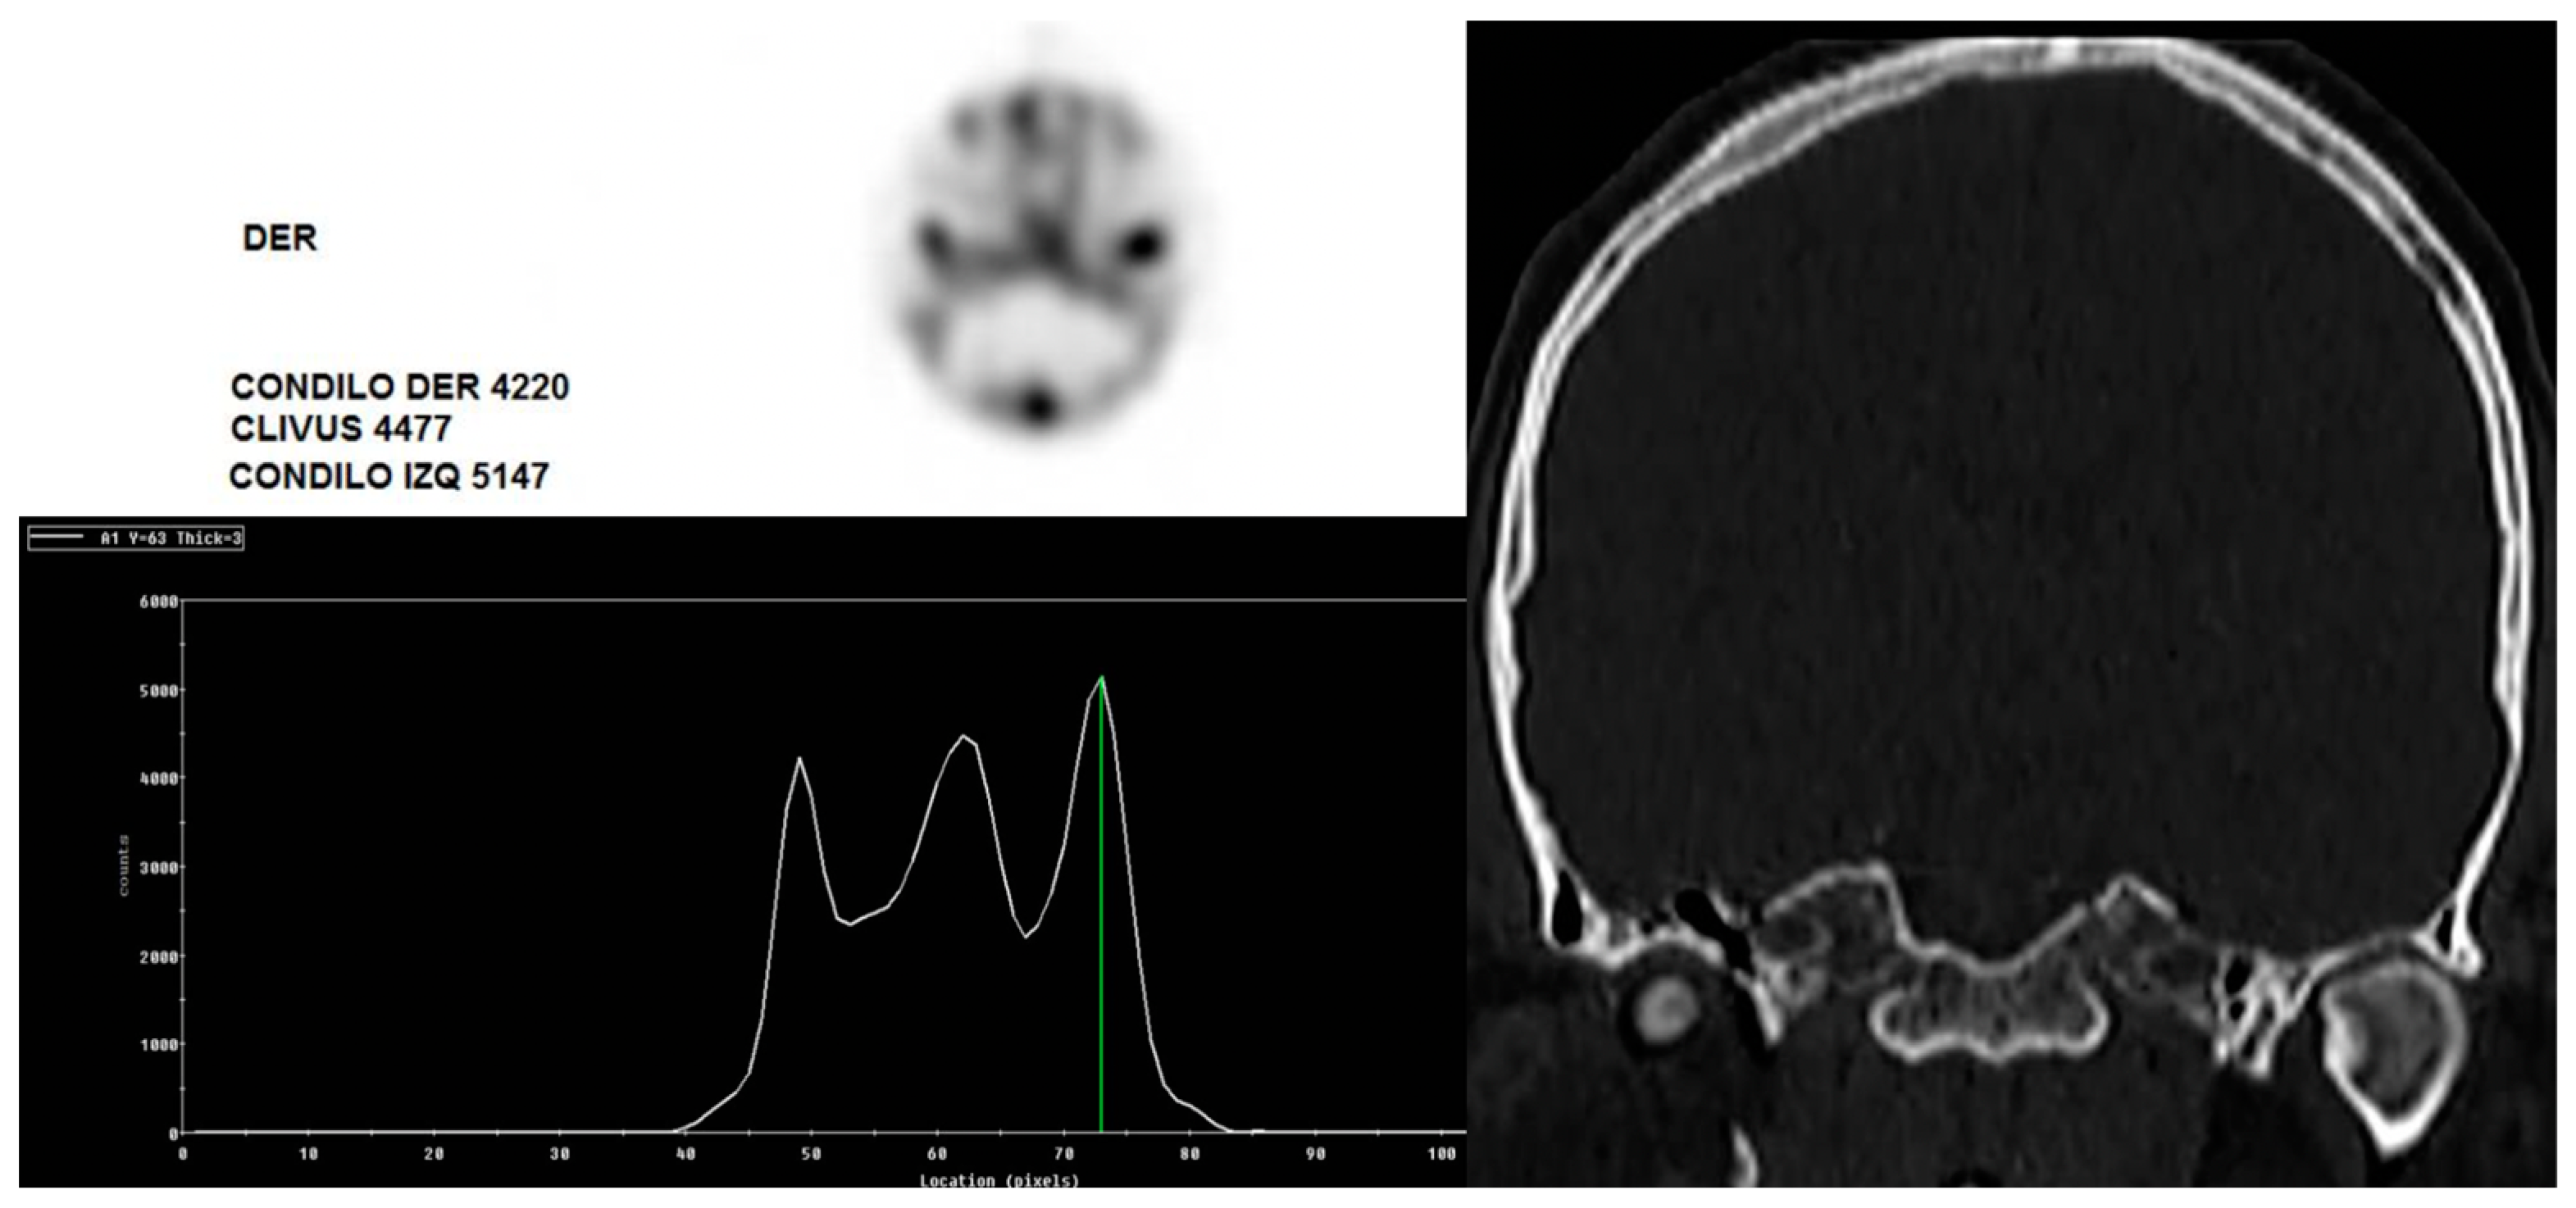

- López, D.F.; Ríos Borrás, V.; Muñoz, J.M.; Cardenas-Perilla, R.; Almeida, L.E. SPECT/CT correlation in the diagnosis of unilateral condilar hyperplasia. Diagnostics 2021, 11, 477. [Google Scholar] [CrossRef] [PubMed]